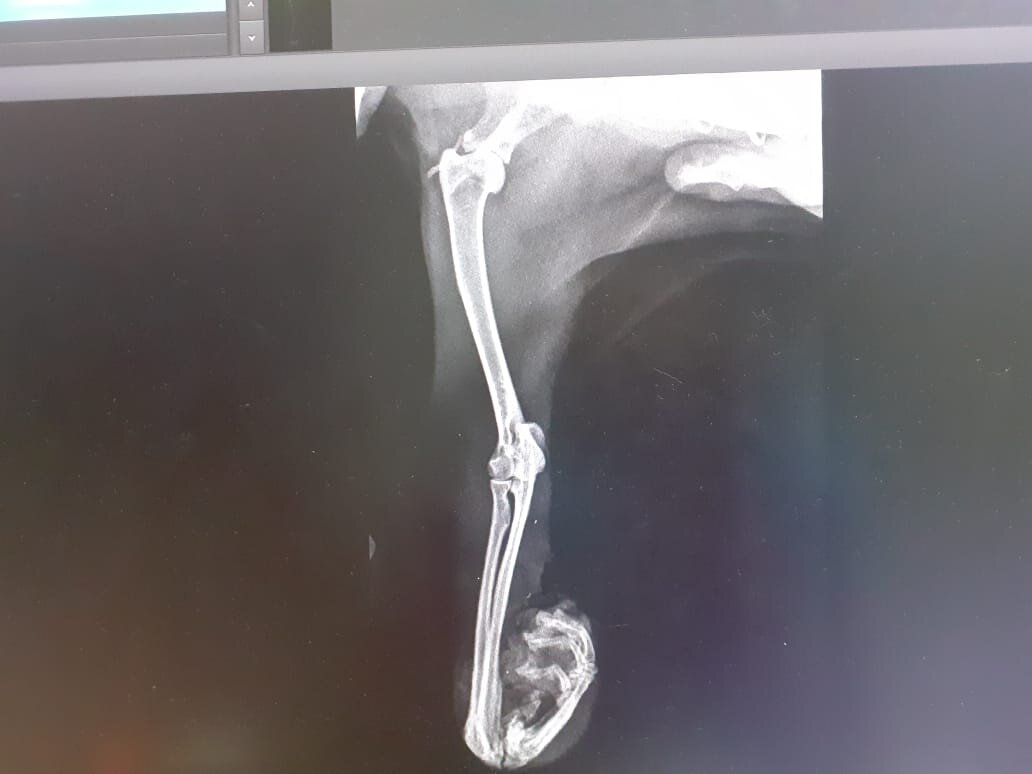

Перелом

На следующий день, вечером, часов в 6, мы повезли кошку к какому-то врачу на обследование,посмотрел, сказал что кровь в лапку поступает, и что гнить она не будет. Ещё сказал, что есть два варианта: ампутация и лечение.